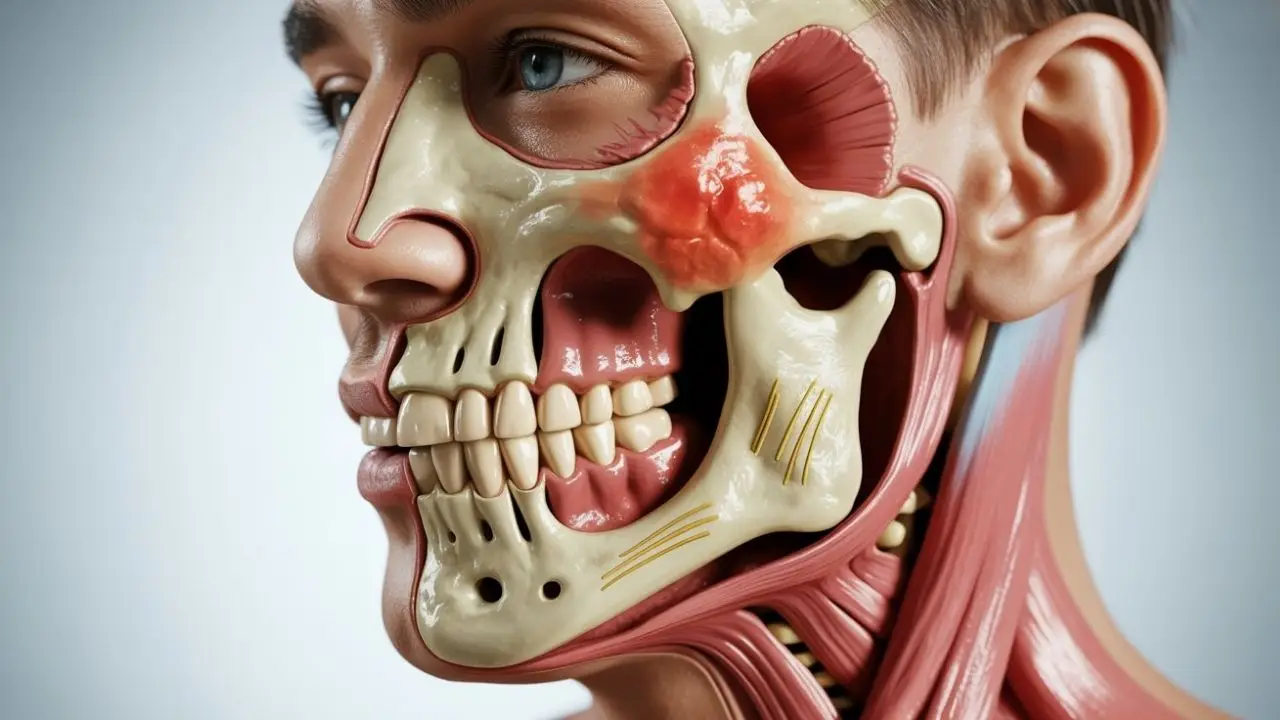

Understanding the Temporomandibular Joint

The temporomandibular joint is one of the most complex joints in the human body. It allows both hinge-like and sliding movements, enabling the jaw to move up and down, side to side, and forward. Because of this complexity, the joint is vulnerable to stress, injury, and muscular imbalance.

Physical and Structural Causes